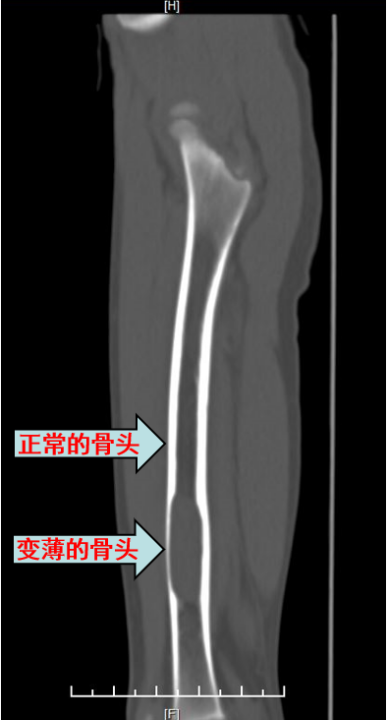

胫骨动脉瘤样骨囊肿病例分享 - 好大夫在线